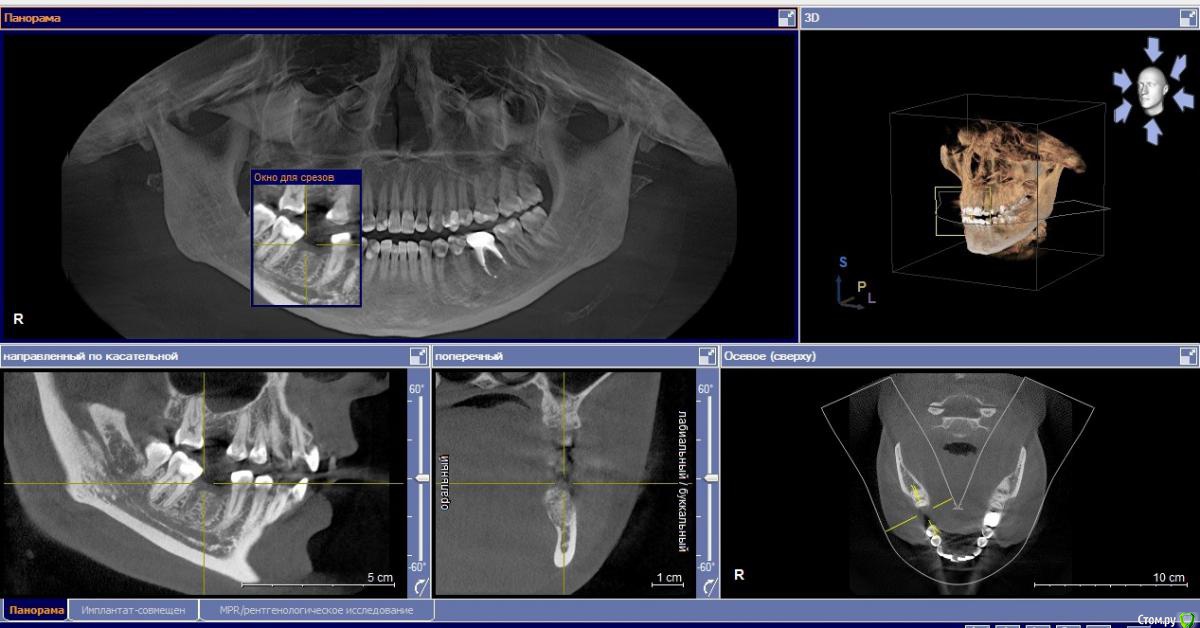

Маргарита19 Опубликовано 22 августа, 2016 Автор Поделиться Опубликовано 22 августа, 2016 Уважаемые стоматологи, помогите, пожалуйста определиться с выбором импланта и схемы лечения. вопрос идет только о 46 зубе, на синус-лифтинг пока не могу решиться. Посетив несколько клиник, стою перед выбором из 2 вариантов: 1. Имплант Нобель Коникал коннекшн (8 мм), временные коронки, потом циркониевые коронки. Но здесь есть еще нюанс, ортодонт советует установить брекеты на нижнюю челюсть, чтобы выровнять передние зубы, там есть небольшая скученность. Сначала подпилить зубы немного по ширине, а потом приклеить брекеты только на 8 зубов, т.к. клыки смыкаются четко. Пока ТРГ и слепков нет, это предварительный план. Меня никогда не беспокоили нижние зубы в плане кривизны. Но, как я поняла, есть нездоровая стираемость зубов. 2. Хирургический шаблон, подсыпать кость искусственную, и Имплант Биотек Коннект (12мм), потом коронки МК, без временных. Про истираемость зубов ничего не сказали, но я и не спрашивала, если честно. Знакомых или проверенных врачей или клиник нет у меня. Вот пытаюсь понять в чьи руки отдаться. Ибо через пол годика хочу решиться на синус и делать его уже имея опыт общения с докторами. Какая схема на ваш взгляд более логичная и какой имлант лучше поставить? Заранее благодарю. Снимки прикрепляю как смогла сделать с КТ. Ссылка на комментарий

Bier Опубликовано 22 августа, 2016 Поделиться Опубликовано 22 августа, 2016 я бы поставил имплантат длиной 8-10мм + подсадка слизистой. По поводу брекетов - имплантата они в данном случае не касаются, это отдельная проблема. 1 Ссылка на комментарий